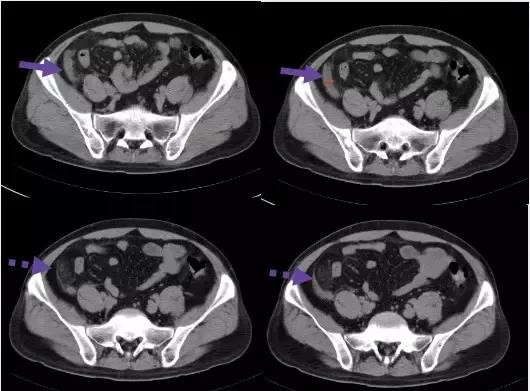

1. 回肠前位:尖端指向左上方

2. 盆位:尖端指向盆腔

3. 盲肠下位:尖端指向右下方

4. 回肠后位:在回肠后位,指向脐

5. 外侧位:位于腹腔内,盲肠外侧